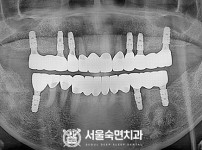

상악동거상술, 뼈이식 / 숙면임플란트 12개 - 오스템임플란트 (김*현님)

해당 게시물은 의료법 제56조에 의거하여 로그인 후 열람이 가능합니다.

구분 임플란트